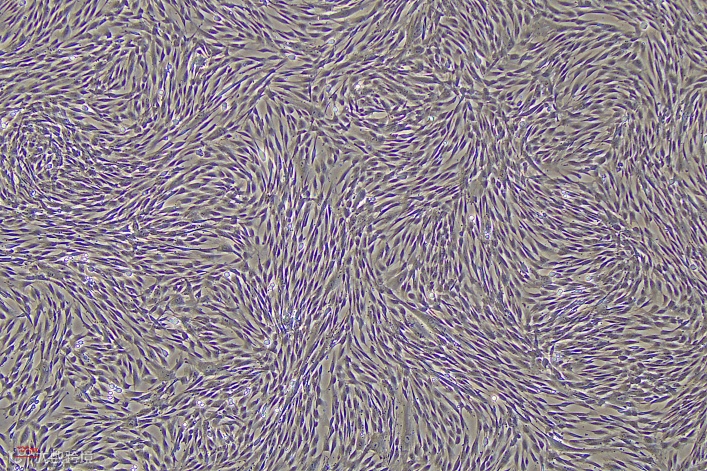

对细胞进行连续传代培养至P10,每代使用UltraTryple 重组温和消化酶进行消化传代。细胞如图2所示,呈梭形、涡旋状排列;P6之前细胞增殖不低于10倍,细胞活率始终维持在97%以上(图3),细胞粒径在14-17um之间(图4)。

图2 MSCs-P6细胞形态